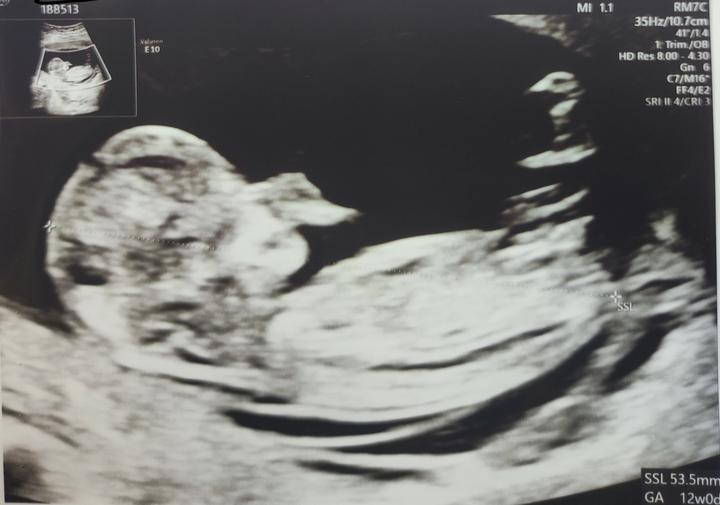

Kedy je citit pohyby babatka cez brusko aj pre inu osobu? Toto si uz fakt nepamatam, deti sa stale pytaju, kedy budu aj oni citit maleho...ja ho uz citim dost dlho, koncime 18.tyzden... Este mesiac? Ci dlhsie? Nevedia sa dockat...

Koncime 16.tyzden a to male v brusku pol dna v pohybe, ze vazne zacinam uvazovat, ze sa nam narodi hypermobilna verzia mladsieho syna 😂 Boh nam pomahaj, ked to fakt tak bude 😅

Po dnesku mame jasno😂Nase duhove babatko bude chlapcek🥰🥰 A hlavne podla rozsirenej genetiky uplne zdravy👍👍